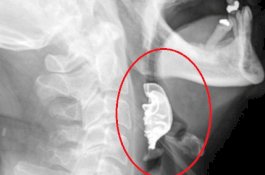

Gigi Palsu Kakek Hilang Sejak Operasi, Ternyata Masuk ke Tenggorokannya